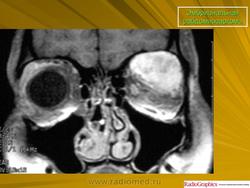

Рабдомиосаркома — чрезвычайно агрессивная опухоль орбиты, является наиболее частой причиной злокачественного роста в орбите у детей. Мальчики болеют почти в 2 раза чаще. Источником роста рабдомиосаркомы являются клетки скелетных мышц. Выделены три типа опухоли: эмбриональный, альвеолярный и плеоморфный, или дифференцированный. Последний тип встречается редко. У детей до 5 лет чаще развивается эмбриональный тип опухоли, после 5 лет — альвеолярный. Как правило, рабдомиосаркома состоит из элементов нескольких типов (смешанный вариант). Точный диагноз можно установить только на основании результатов электронной микроскопии.

Излюбленная локализация опухоли — верхневнутренний квадрант орбиты, поэтому в процесс рано вовлекаются мышца, поднимающая верхнее веко, и верхняя прямая мышца. Птоз, ограничение движений глаза, смещение его книзу и книзу кнутри — это первые признаки, на которые обращают внимание как сами больные, так и окружающие лица. У детей экзофтальм или смещение глаза при локализации опухоли в переднем отделе орбиты развивается в течение нескольких недель (рис. 20.23, а). У взрослых опухоль растет медленнее, в течение нескольких месяцев. Быстрое увеличение экзофтальма сопровождается появлением застойных изменений в эписклеральных венах, глазная щель полностью не смыкается, отмечаются инфильтраты на роговице и ее изъязвление. На глазном дне — застойный диск зрительного нерва. Первично развиваясь вблизи верхневнутренней стенки орбиты, опухоль быстро разрушает прилежащую тонкую костную стенку, прорастает в полость носа, вызывая носовые кровотечения. Ультразвуковое сканирование, компьютерная томография, термография и тонкоигольная аспирационная биопсия — это оптимальный диагностический комплекс инструментальных методов исследования при рабдомиосаркоме (рис. 20.23, б). Лечение комбинированное. Протокол лечения предусматривает предварительное проведение полихимиотерапии в течение 2 нед, после чего проводят наружное облучение орбиты. После комбинированного лечения более 3 лет живут 71 % больных.